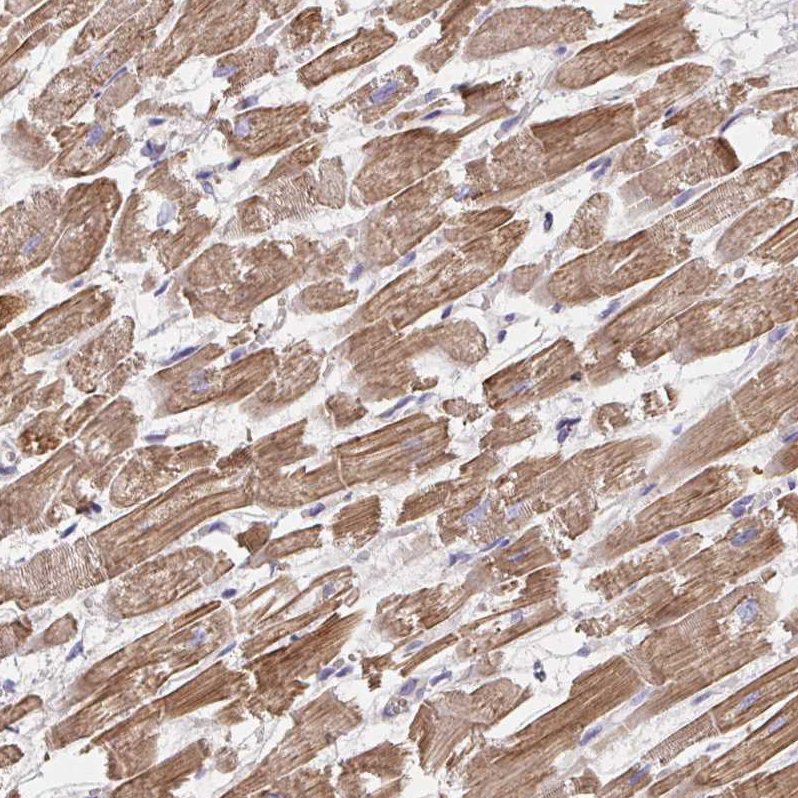

Immunohistochemical staining of human heart muscle shows moderate to strong cytoplasmic positivity in cardiomyocytes.